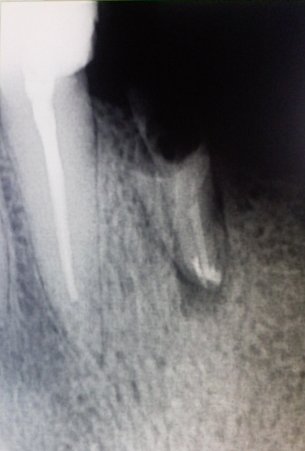

У меня треснул зуб (семерка нижняя), в нем стоит пломба, уже давно, но полтора года назад меняла т.к. старая вылетела. Тогда же и удалили нервы. Вчера ночью лопнул зуб. Отошла от пломбы часть с внутренней стороны, где язык и часть, где стык с восьмеркой. Лопнул до основания, держится на десне. Вырывать сама боюсь. Шестерки рядом уже нет, лет пять. Не хочу удалять и этот зуб.

Все зависит от характера скола стенки, если разрушение ниже уровня десны, то, к сожалению, зуб удаляется, хотите вы этого или нет. Причина скола кроется в неправильном решении, полтора года назад необходимо было вместо пломбы восстанавливать зуб коронкой и в этом случае ничего бы не произошло. Обратитесь к врачу, окончательный диагноз можно поставить на очном приеме.